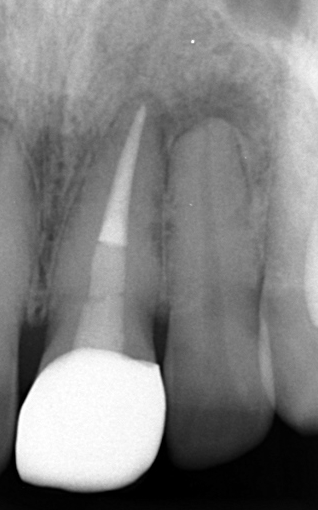

3. 偶発的に見つかった「歯根の内部吸収」

本症例において、主訴ではない左上顎中切歯には「歯根の内部吸収」を認めました。レントゲン撮影時に偶発的に見つかった所見です。

歯根吸収は進行して歯質が菲薄化しており、いつ折れてもおかしくない状況でした。内部吸収は根管治療で進行を止められる可能性がありますが、失われた歯質は回復しません。残存歯質量の少なさから、保存的治療は困難と判断し、患者様にご説明いたしました。 (※永久歯の歯根吸収は原因不明なことも多いですが、お話を伺う限り、過去の外傷を起因とするものと推察されました。)

右上顎中切歯:精密根管治療後にセラミッククラウンによる補綴処置

治療前後の写真です。ホワイトニングも行い、口腔内全体が明るい印象になりました。 レントゲンでは、右上顎中切歯の透過像は縮小しており、根尖性歯周炎は治癒傾向にあります。